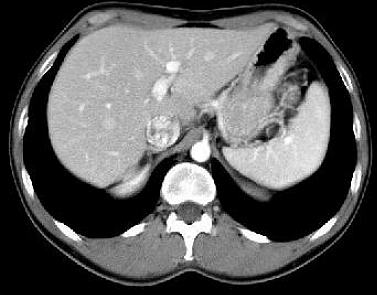

the pathological image-left and the physiological image-right

If you need a physiological

image to compare click here